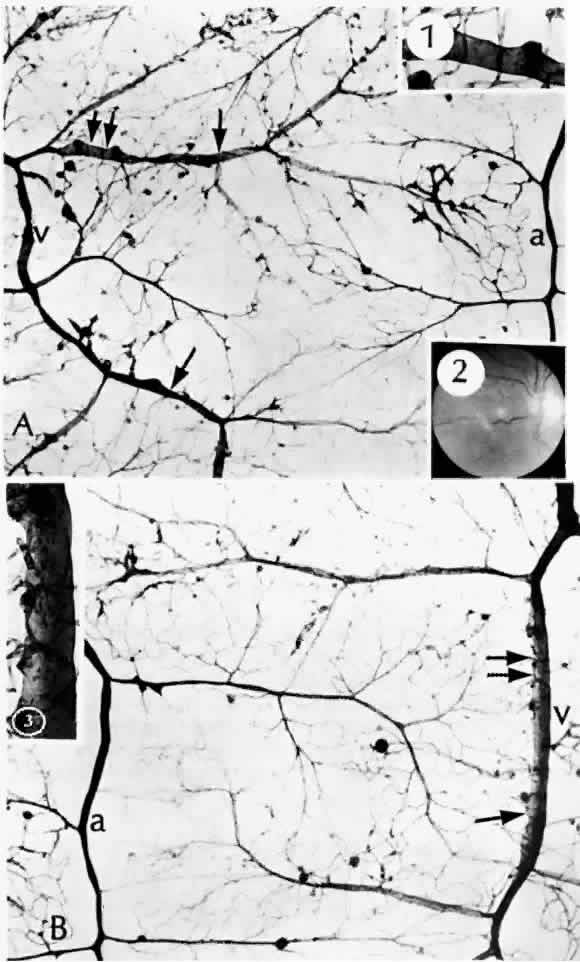

The retinal veins can also become irregular and tortuous with sausage-shaped dilatations. The vascular walls become diffusely permeable so that they both leak and stain with fluorescein. These changes also seem to be associated with ischemia. As shown by trypsin digestion, the beaded areas are hypercellular (Fig. 10).43 Diabetes is also a risk factor for branch retinal vein occlusion47 and central vein occlusion.43

Fig. 10. A and B. Sausage-shaped venules (arrows) result from irregularities in the venular walls. Note the arteriolar-venular connections and thickened capillary basement membranes (dark-colored capillaries). Retinal capillary microaneurysms tend to arise from cellular (viable) capillaries and cluster around acellular (nonviable) capillaries. The venular walls not only are irregular, but they also have an unusual presence of saccular microaneurysms (Inset 1, and Inset 3 from the area of the double arrows). Inset 2. Fundus appearance of microaneurysms, a cotton-wool spot, irregular venules, and intraretinal neovascularization in the form of a rete mirabile. (a = arteriole; v = venule) (A and B, PAS, × 16; Inset 1, PAS, × 40; Inset 2, fundus; Inset 3, PAS × 54)